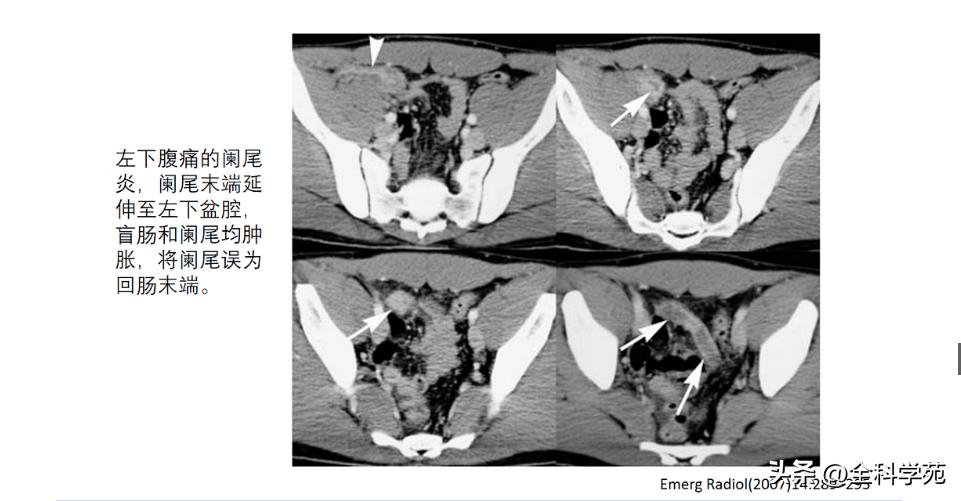

▪ 沿着结肠,从直肠到右半结肠,找到回盲部复合体,在回盲瓣下方2-3厘米处寻找一个盲管状消化道结构

尖端阑尾炎、臀部阑尾炎(残余阑尾组织大于5mm,0.15%),右下腹脓肿